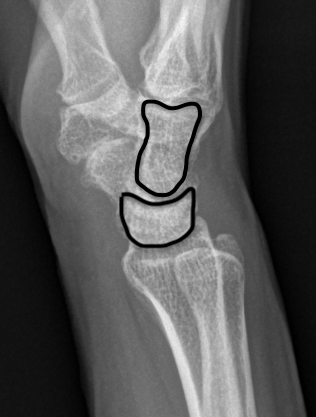

Gilula carpal arcs

| Giluala carpal arcs | Arc injuires |

|---|---|

|

Normally there are 3 smooth carpal arcs on PA xray

Arc I: Proximal cortical margins of proximal carpal row Arc II: Distal carpal margin of the proximal carpal row Arc III: Proximal cortices of the capitate and hamate |

Greater arc injuries - ligamentous injury + fracture - fractures of scaphoid / capitate / radial styloid - scaphoid most common, radial styloid second)

Lesser arc injuries - Purely ligamentous injuries around the lunate

AP X-ray

Disruption of Gilula's 3 smooth carpal arcs / triangular lunate

Normal versus disruputed Gilula's carpal arcs

Piece of pie / triangular appearance of lunate